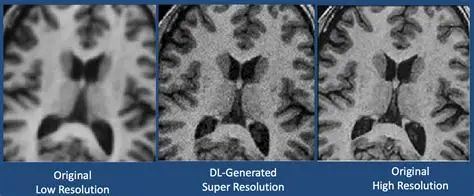

Carving 3D Anatomy Out of Noisy Scans

Our collaboration with Duke University’s medical school supplied us with rich—but messy—volumes of CT and MRI scans. The goal: segment complex organs and vasculature in full 3D so surgeons and researchers can study change over time, not just slice by slice. What we built Why it was hard Three-dimensional data is huge. Memory pressure forced us to invent chunked training…